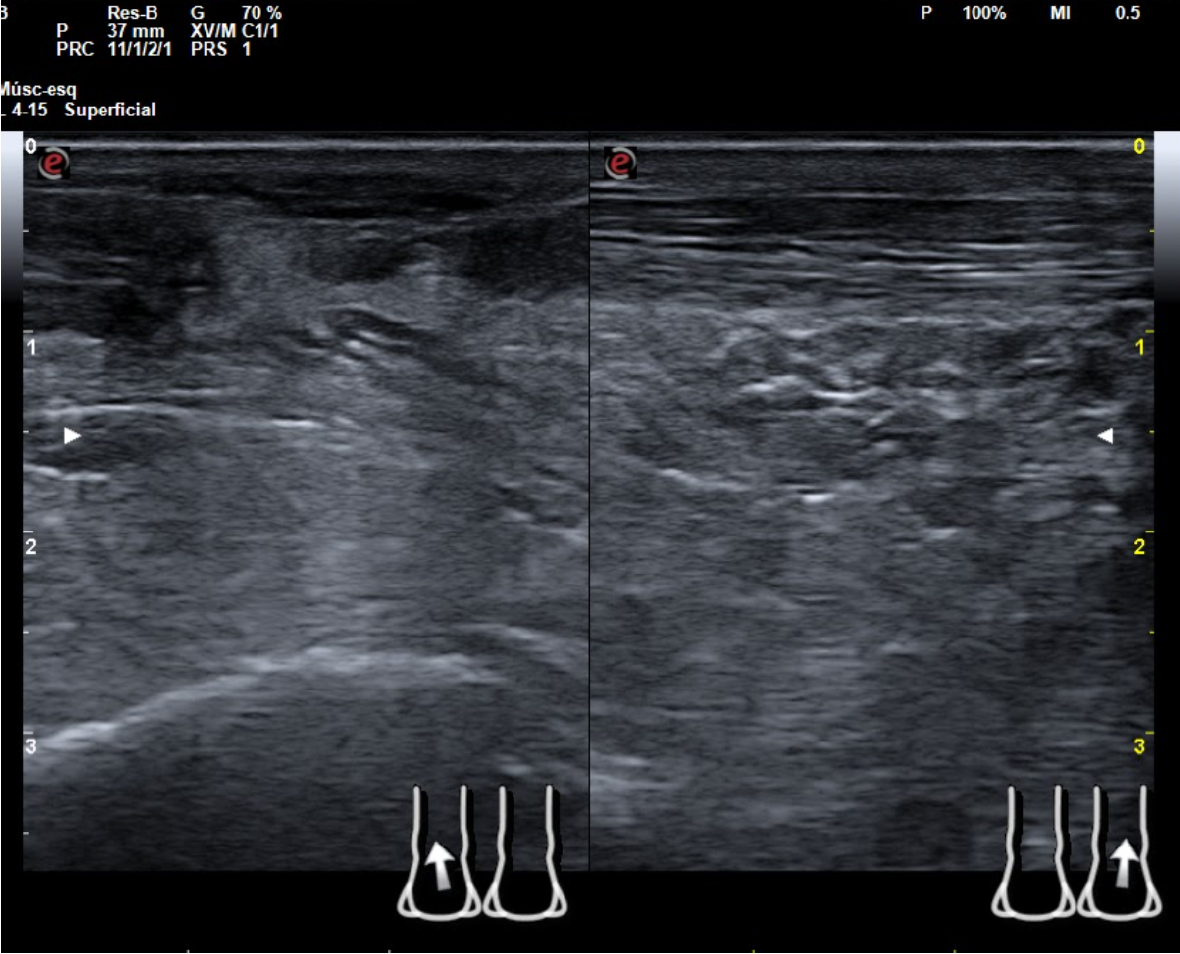

Hallazgos ecográficos

En tendón aquíleo izquierdo se aprecia rotura completa con solución de continuidad de 2 cm localizada a 5,7 cm de su inserción en el calcáneo. Presenta áreas hipoecoicas peritendón que sugieren hematoma secundario. En el aquíleo derecho presenta leve hipoecogenicidad y engrosamiento del tendón sin solución de continuidad que sugiere tendinosis. Importante componente inflamatorio. No datos de TVP. Poplítea y safena externa permeables y compresibles en ambas extremiedades.

Juicio clínico: Rotura completa de tendón de Aquiles izquierdo. Tendinosis aquílea derecha.